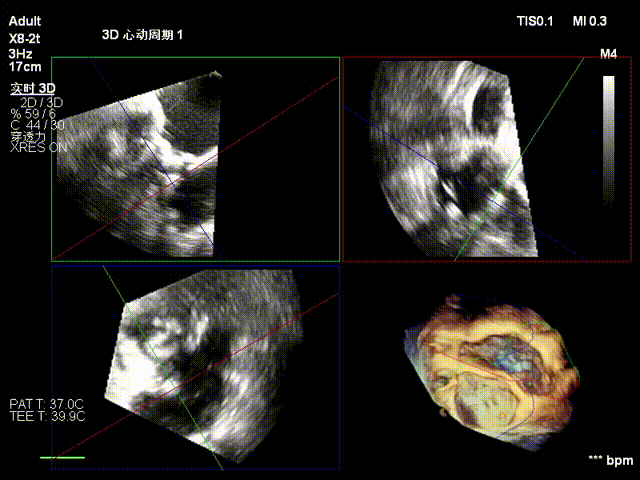

经右颈内静脉穿刺建立通路,置入18Fr鞘管,将K-Clip®输送系统送达右心房。依托三维经食管超声心动图(3D TEE)联合 DSA 双模态引导,经验精准定位瓣环,于后隔交界(P-S commissure)植入14T规格K-Clip®,前后交界(A-P commissure)植入16T规格K-Clip®,实现瓣环多点精准环缩。每枚夹子释放后,团队实时通过超声评估瓣叶对合及反流改善情况,严格遵循 “精准定位 - 锚定验证 - 安全解离” 的规范化操作流程,确认无瓣叶损伤、瓣口狭窄及心包并发症后,完成器械解离与撤出。

2. 超声引导下置入大鞘和输送系统